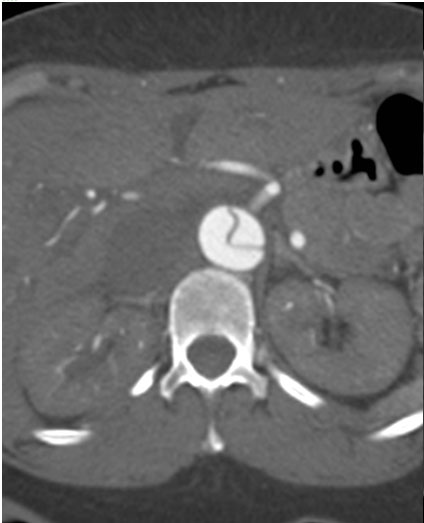

The patient underwent repeat CTA 1 month later which demonstrated thrombosis of the false lumen except for a 4.5 x 4.6cm pseudoaneurysm proximal to the distal repair. (Figure 4) Since the new finding appeared to have a defined neck, the possibility of an endovascular exclusion of the fenestration was discussed with the back-up plan being either open or hybrid arch replacement. The patient underwent a carotid subclavian bypass using an 8mm Gore-Tex ring graft (WL Gore & Associates Inc, Flagstaff, AR) to extend the proximal landing zone. Aortic coverage was planned from the combined origin of the brachiocephalic and left common carotid arteries (bovine arch anatomy) down into the previously placed tube graft. Two days later, two Cook TX2 thoracic endografts (Cook Inc, Bloomington, IN) 30 x 120mm and 36 x 127mm were overlapped to exclude the intimal defect. Completion angiography demonstrated contrast in the proximal subclavian without perfusion of the false lumen. (Figure 5)

Figure 5a. Intraoperative angiogram demonstrating 4.4 x 4.6cm pseudoaneurysm distal to the left subclavian artery.

Figure 5b. Angiography after carotid-subclavian bypass and exclusion of pseudoaneurysm with a Cook TX2 thoracic graft. Note bovine arch anatomy with combined origin of brachiocephalic and carotid arteries.